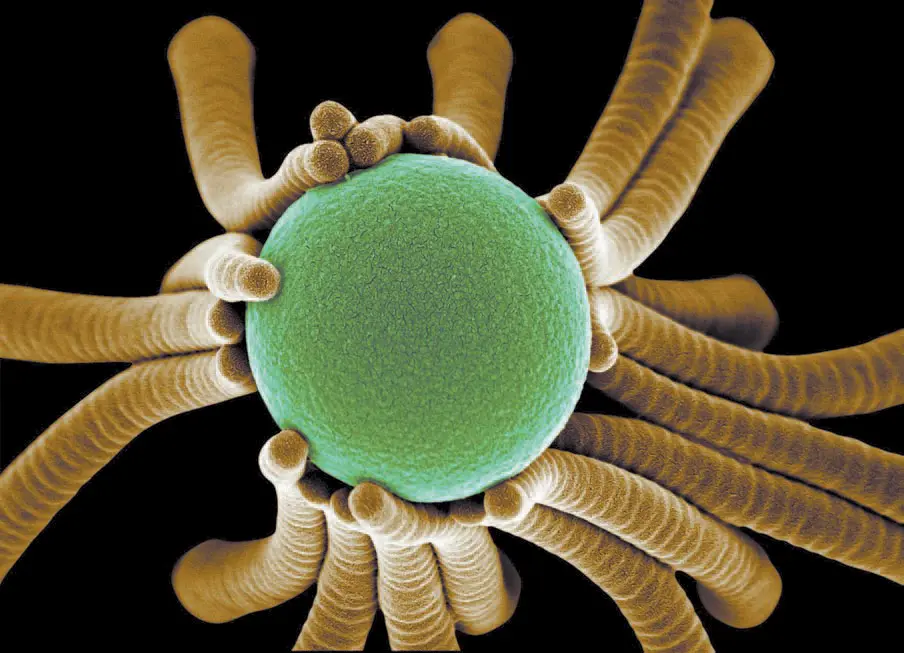

Компьютерная томограмма носа 33-летней пациентки с болезнью щитовидной железы, вид от ноздрей Сredit: Kai-hung Fung, Pamela Youde Nethersole Eastern Hospital